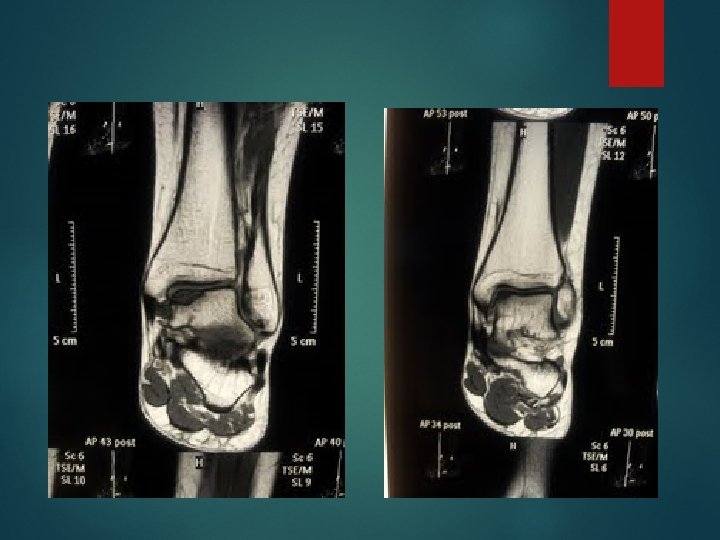

Hondralna lezija talusa